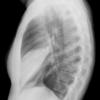

Case 2 Lingular pneum PA

Date: 04/17/2005

Views: 5944